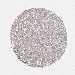

LIVER CANCER - Protein expressioni

A mouse-over function shows sample information and annotation data. Click on an image to view it in a full screen mode. Samples can be filtered based on level of antibody staining by selecting one or several of the following categories: high, medium, low and not detected. The assay and annotation is described here.

Note that samples used for immunohistochemistry by the Human Protein Atlas do not correspond to samples in the TCGA dataset.

Antibody stainingi

Antibody staining in the annotated cell types in the current human tissue is reported as not detected, low, medium, or high, based on conventional immunohistochemistry profiling in selected tissues. This score is based on the combination of the staining intensity and fraction of stained cells.

Each image is clickable and will lead to virtual microscopy that enables deeper exploration of all samples and also displays staining intensity scores, fraction scores and subcellular localization as well as patient and tissue information for each sample.

HPA046356

HPA048287

HPA050103

CAB009811

CAB032603

Staining

High

Medium

Low

Not detected

Intensity

Strong

Moderate

Weak

Negative

Quantity

>75%

75%-25%

<25%

None

Location

Nuclear

Cytoplasmic/membranous

Cytoplasmic/membranous,nuclear

Cholangiocarcinoma

Carcinoma, Hepatocellular, NOS